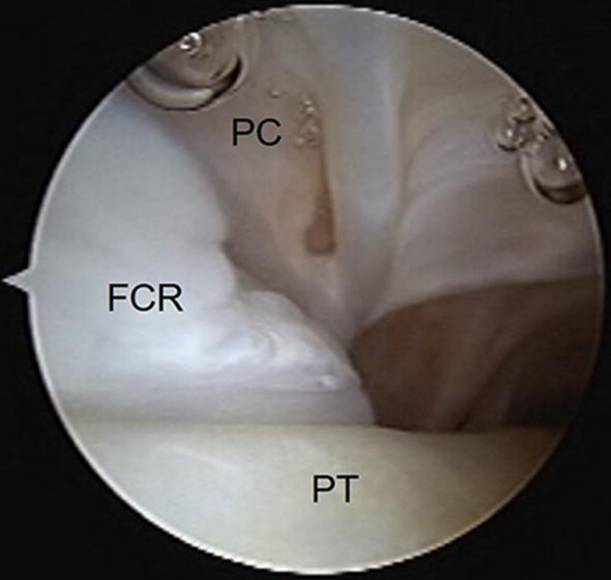

PC 假腔,FCR 纤维软骨脊,PT 腓骨肌腱。图源:DOI:10.1007/s00167-020-05877-x